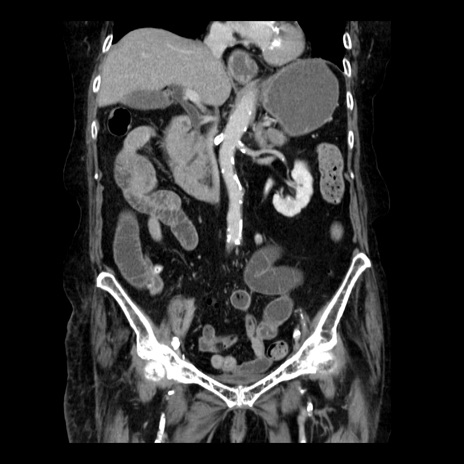

症例14(冠状断像)

【症例】 90歳代女性

【主訴】 腹痛・嘔吐

【現病歴】今朝から左側腹部痛を認めた。 経過観察していたが、嘔吐を認めたため来院。

【既往歴】 子宮癌術後

【身体所見】 意識清明、BP 127/54mmHg、P 98bpm Sp02 95%(RA)、BT 35.8°C、腹部平坦・軟腸ぜん動音聴取良好、右下腹部圧痛(+) 反跳痛なし

【データ】WBC 9800、CRP 0.46